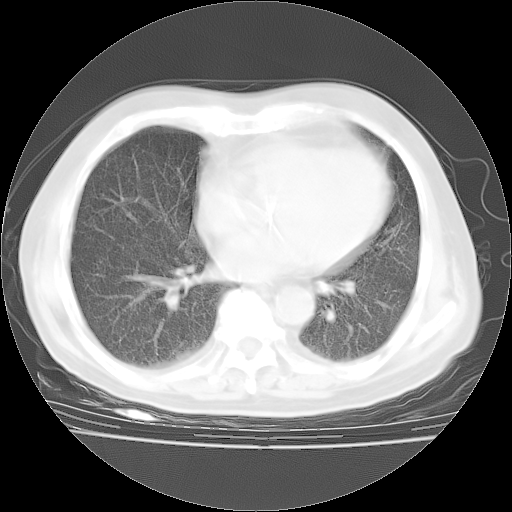

4月28日肺部CT——再次出现类似去年5月9日——磨玻璃样、间有“粟粒样”改变。

4月28日肺部CT